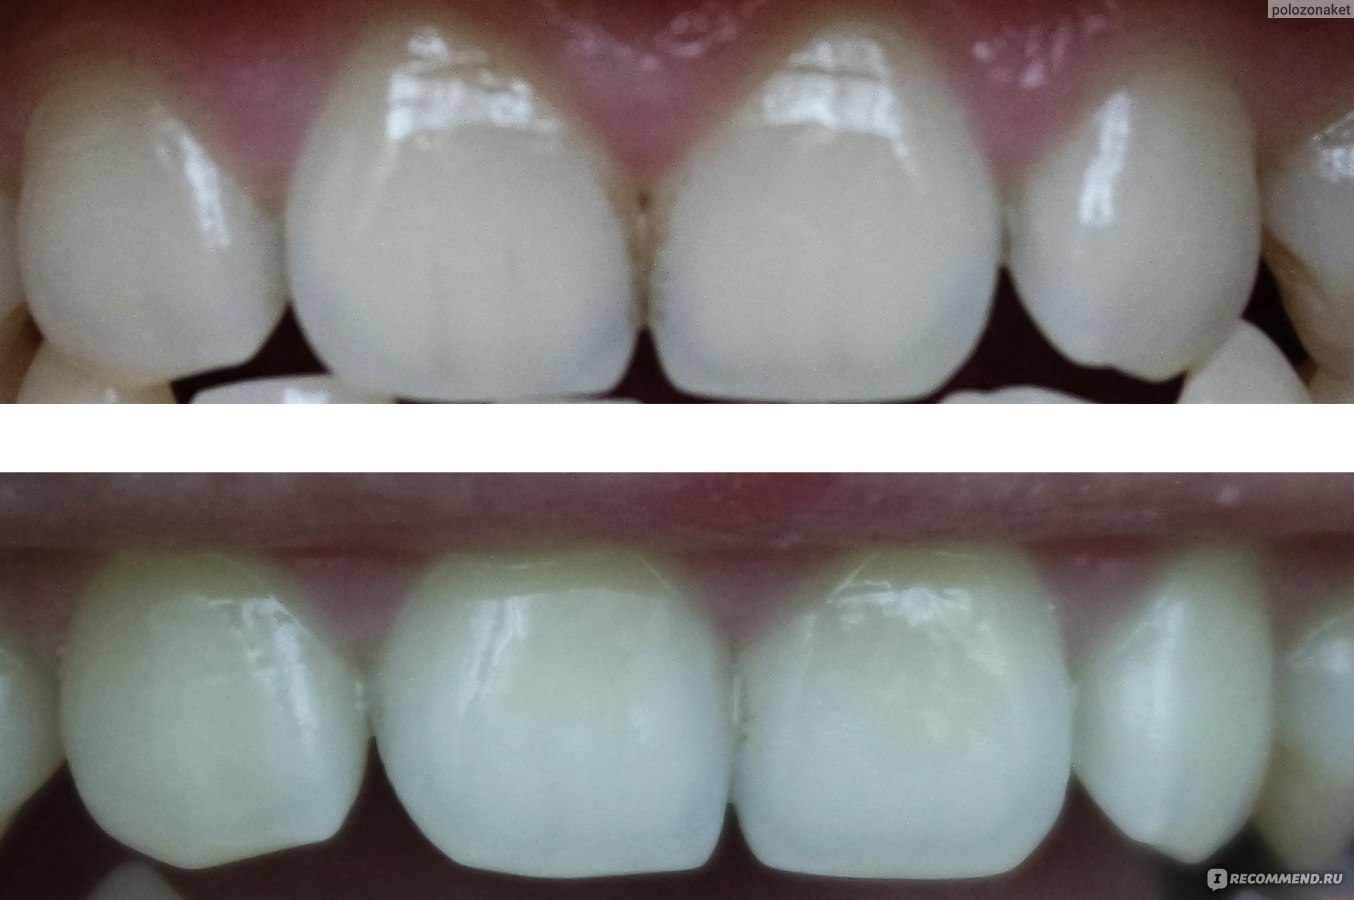

Иллюстрации флюороза молочных зубов

Раздел: Необычные решения